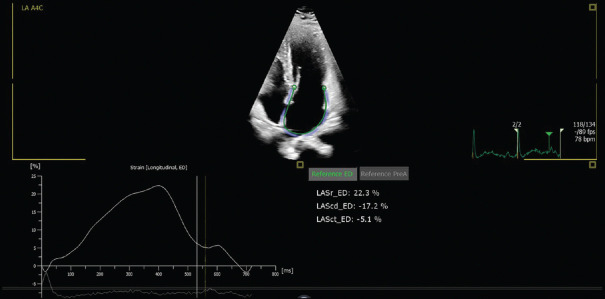

Abstract Image